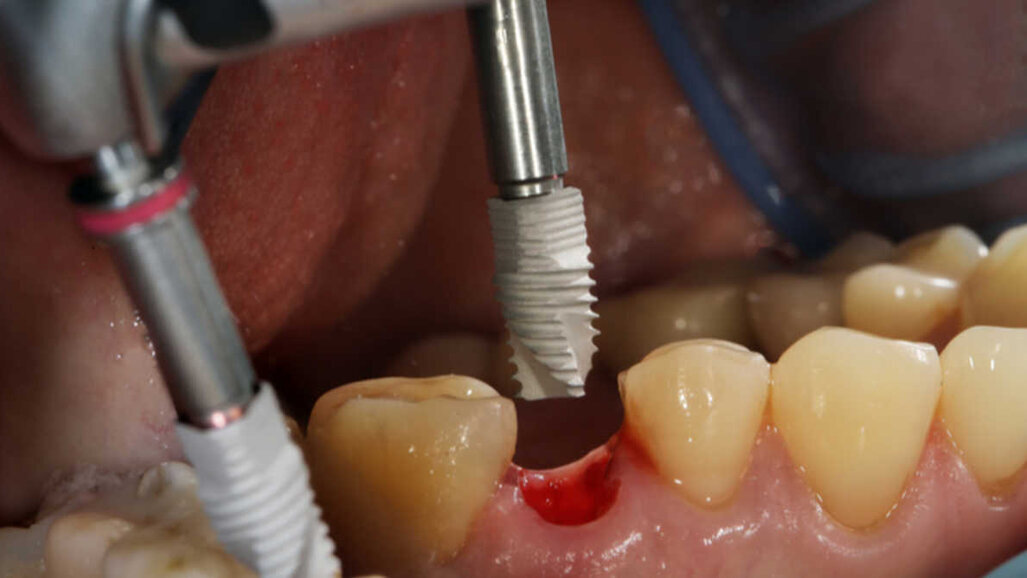

ANKARA, Turecko: Použití standardních zubních implantátů se stalo široce akceptovanou metodou ošetření u zcela nebo částečně bezzubých pacientů. V případě závažných alveolárních resorpcí však není možné použití implantátu standardní délky bez dodatečného chirurgického zákroku. V takových případech je možnost použití krátkých implantátů považována za velký přínos pro implantologii. Nedávná studie však nyní odhalila rizikové faktory pro udržení krátkých implantátů.

Cílem studie, provedené ve spolupráci univerzity Ankara Yildirim Beyazit v Ankaře, univerzity Cumhuriyet University v Sivas v Turecku a soukromé zubní ordinace v Ankaře, bylo zjistit různé rizikové faktory, související s implantáty i pacienty, podílející se na dlouhodobé úspěšnosti krátkých dentálních implantátů. Prostřednictvím retrospektivního přehledu ze tří center byly shromážděny informace o pacientech, týkající se demografických proměnných, jako jsou kouření, anamnéza periodontitidy či systémových onemocnění a medikace. Kromě toho byly shromážděny informace týkající se parametrů umístěných krátkých implantátů, včetně výrobce implantátu, jeho tvaru, anatomického umístění, průměru a délky a typu zavedení.